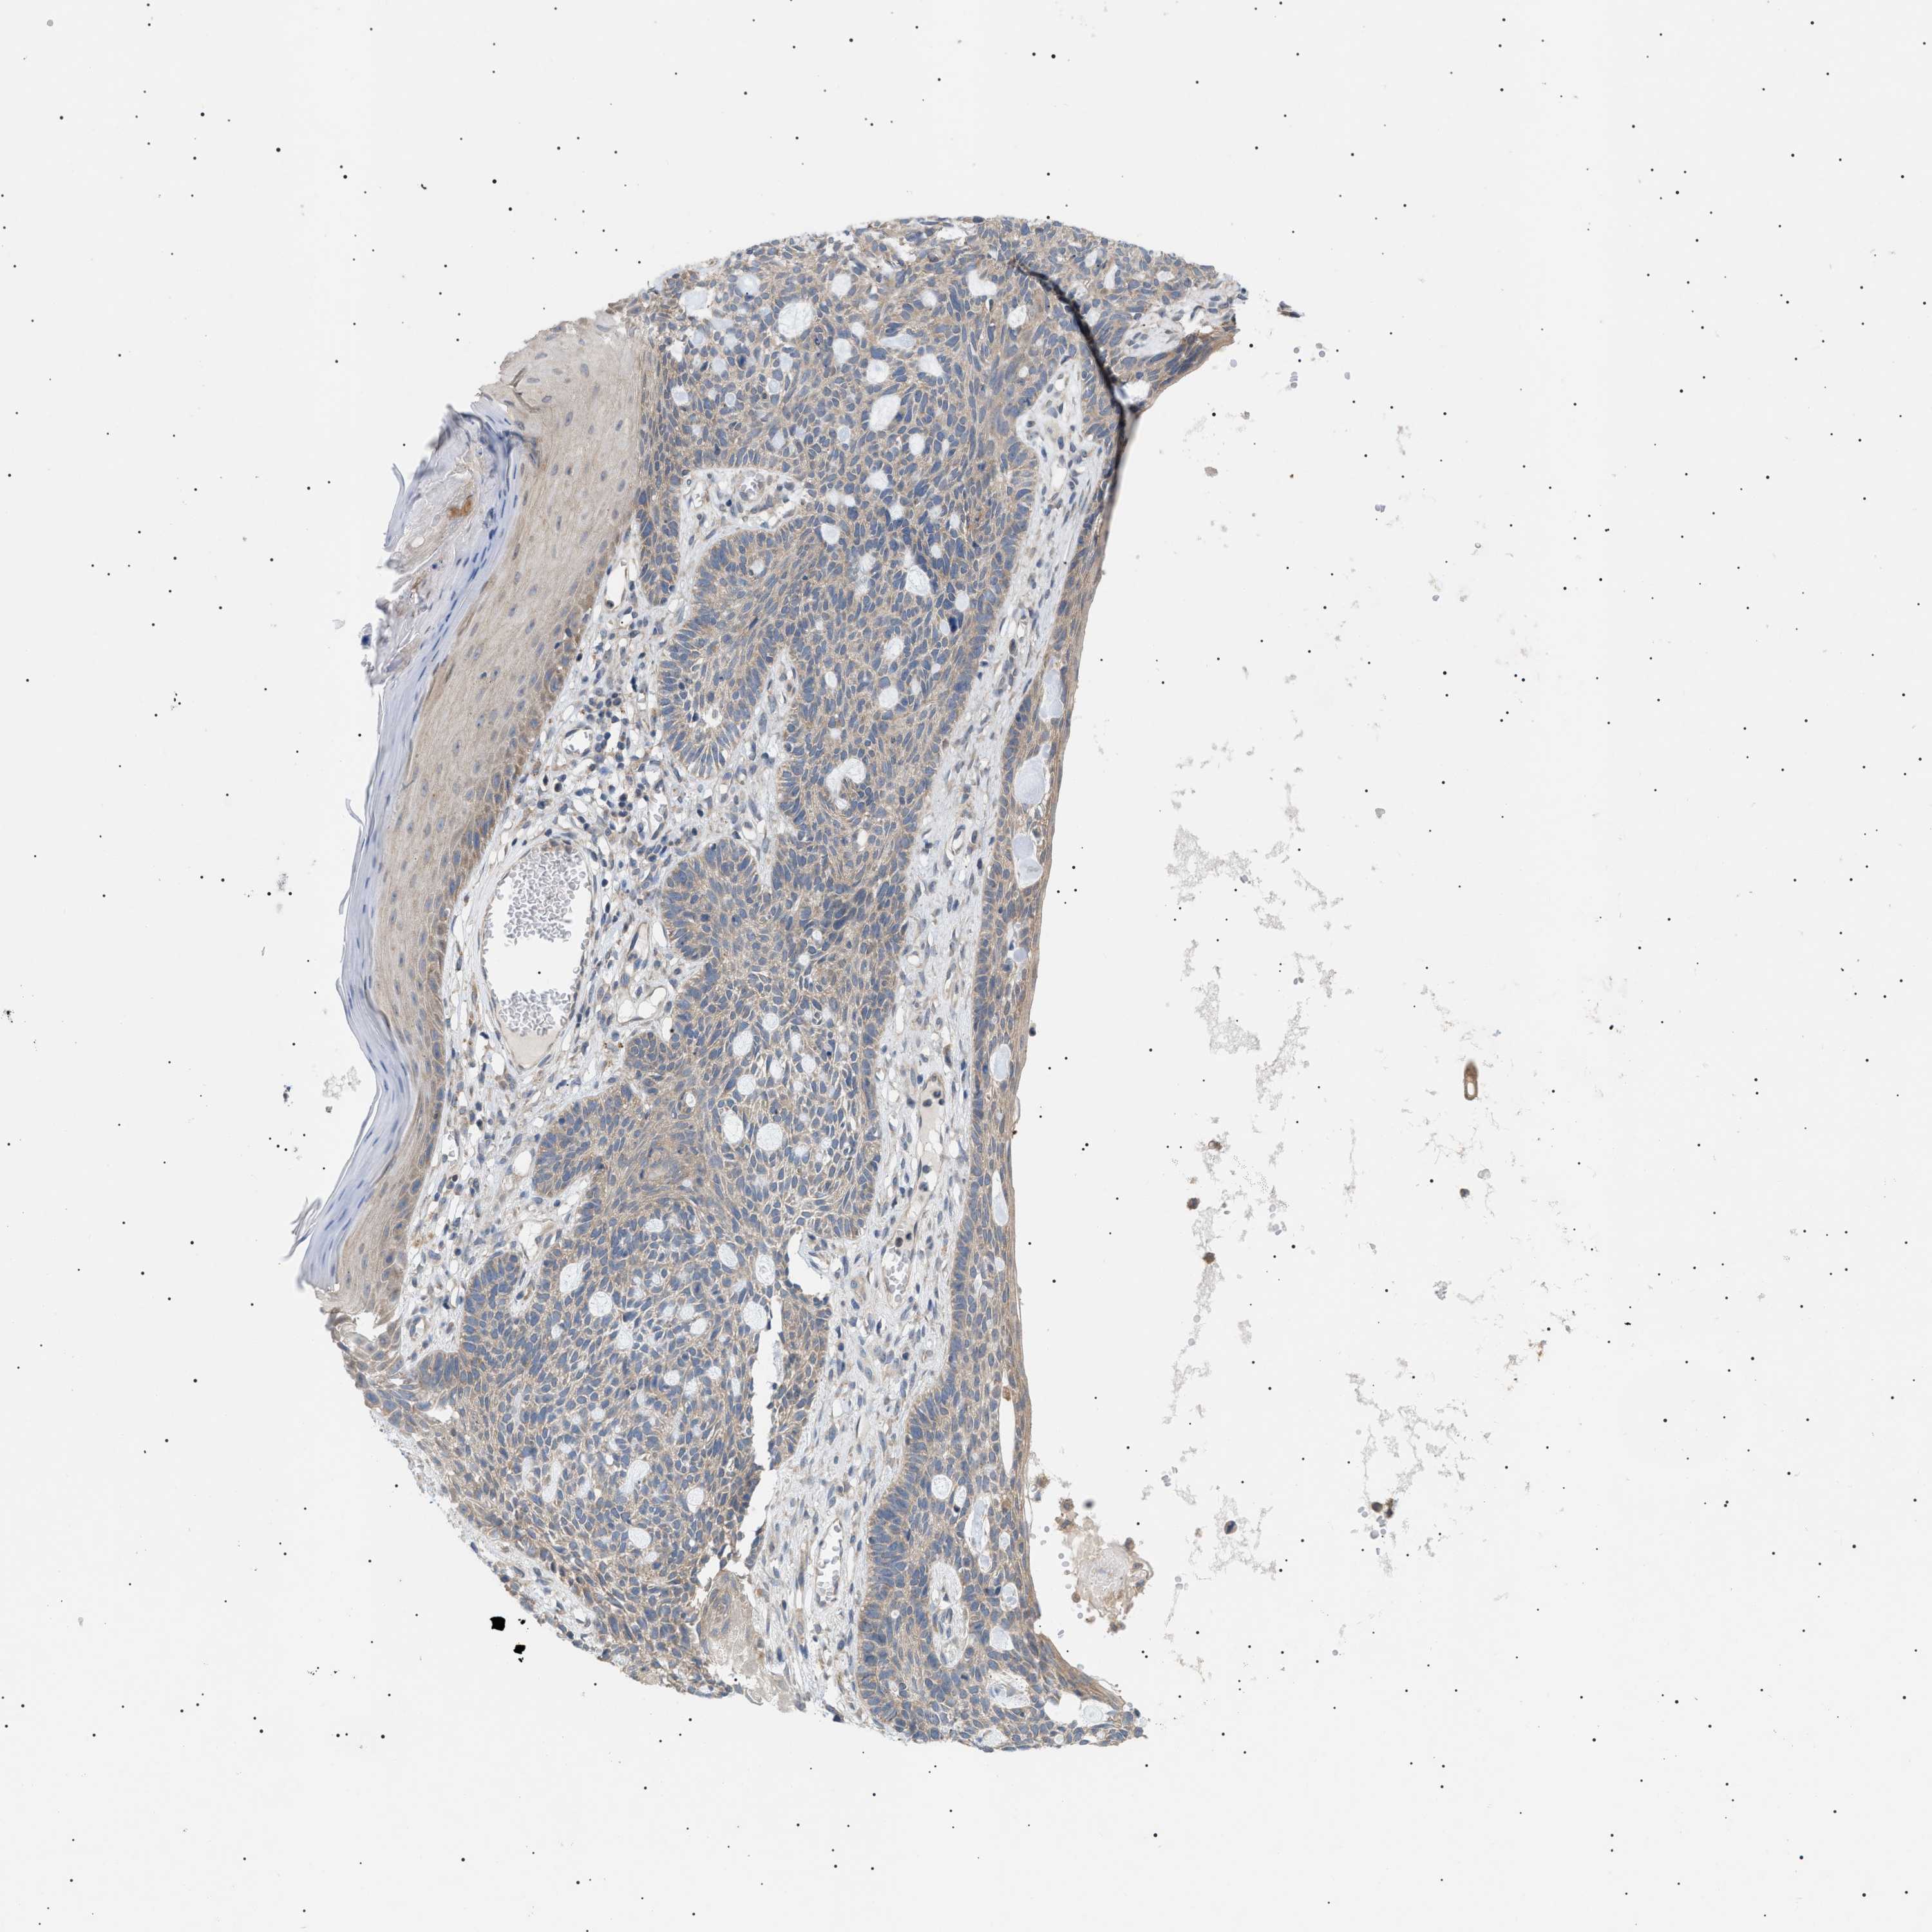

Basal cell and squamous cell cancer

SKIN CANCER - Protein expressioni

A mouse-over function shows sample information and annotation data. Click on an image to view it in a full screen mode. Samples can be filtered based on level of antibody staining by selecting one or several of the following categories: high, medium, low and not detected. The assay and annotation is described here.

Note that samples used for immunohistochemistry by the Human Protein Atlas do not correspond to samples in the TCGA dataset.

Antibody stainingi

Antibody staining in the annotated cell types in the current human tissue is reported as not detected, low, medium, or high, based on conventional immunohistochemistry profiling in selected tissues. This score is based on the combination of the staining intensity and fraction of stained cells.

Each image is clickable and will lead to virtual microscopy that enables deeper exploration of all samples and also displays staining intensity scores, fraction scores and subcellular localization as well as patient and tissue information for each sample.

Antibody CAB016944

Staining

High

Medium

Low

Not detected

Intensity

Strong

Moderate

Weak

Negative

Quantity

>75%

75%-25%

<25%

None

Location

Nuclear

Cytoplasmic/membranous

Cytoplasmic/membranous,nuclear

Squamous cell carcinoma in situ, NOS

Squamous cell carcinoma, NOS

Squamous cell carcinoma, metastatic, NOS

Basal cell carcinoma

Adnexal tumor, benign